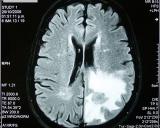

Какую роль играет компьютерная томография при диагностике острого ишемического инсульта. Тема была обсуждена специалистами в ходе дискуссии в МЦ ЭРЕБУНИ. Стартовавшая с февраля 2019г. государственная...